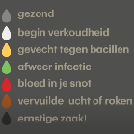

Snot

Snot kan er op veel manieren uitzien. Snot zegt soms iets over de oorzaak van de neusaandoening. Er kan een onderscheid gemaakt worden tussen helder, wit, geel, groen, rood, bruin en zwart snot.